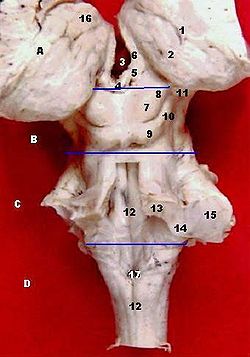

| Human brainstem mesencephalon (B) | ||

فى علم التشريح فإن ال, mesencephalonأو ( دماغ متوسط) يشمل tectum (أو corpora quadrigemini), tegmentum, the ventricular mesocoelia أو( "iter"), و الcerebral peduncles, بالإضافة الى العديد من nuclei و fasciculi. Caudally ال mesencephalon يرتبط ب pons (metencephalon) و يرتبط ب diencephalon (Thalamus, hypothalamus, et al).

Midbrain and hindbrain are grouped together and called the brain stem.

إن التقاء الدماغ المتوسط والخلفي يشكل ما يسمى بجذع المخ.

Corpora Quadrigemina

The corpora quadrigemina ("quadruplet bodies") are four solid optic lobes on the dorsal side of cerebral aqueduct, where the superior posterior pair are called the superior colliculi and the inferior posterior pair are called the inferior colliculi. The four solid optic lobes help to decussate several fibres of the optic nerve. However some fibers also show ipsilateral arrangement (i.e. they run parallel on the same side without decussating.) The superior colliculus is involved with saccadic eye movements; while the inferior is a synapsing point for sound information. The trochlear nerve comes out of the posterior surface of the midbrain, below the inferior colliculus.

Cross-Section Through the Midbrain

The midbrain is usually sectioned at the level of the superior and inferior colliculi.

A cross-section at the level of the superior colliculus shows the red nucleus, the nuclei of the oculomotor nerve (and associated Edinger-Westphal nucleus), as well as the substantia nigra.

The substantia nigra is still present at inferior colliculus level. Also apparent are the trochlear nerve nucleus, and the decussation of the superior cerebellar peduncles.

The cerebral aqueduct runs through the midbrain, and is the communication between the third and fourth ventricle.

As a mnemonic the mesencephalic cross-section resembles a bear (or teddybear) upside down with the two red nuclei as the eyes and the crus cerebri as the ears.

Diagram of the midbrain, sectioned at the level of the superior colliculus